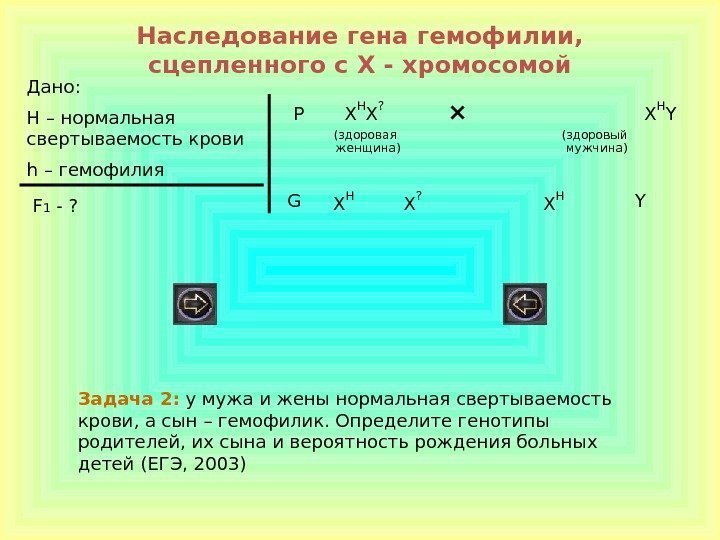

Генетика гемофилии: рецессивные гены и их проявления